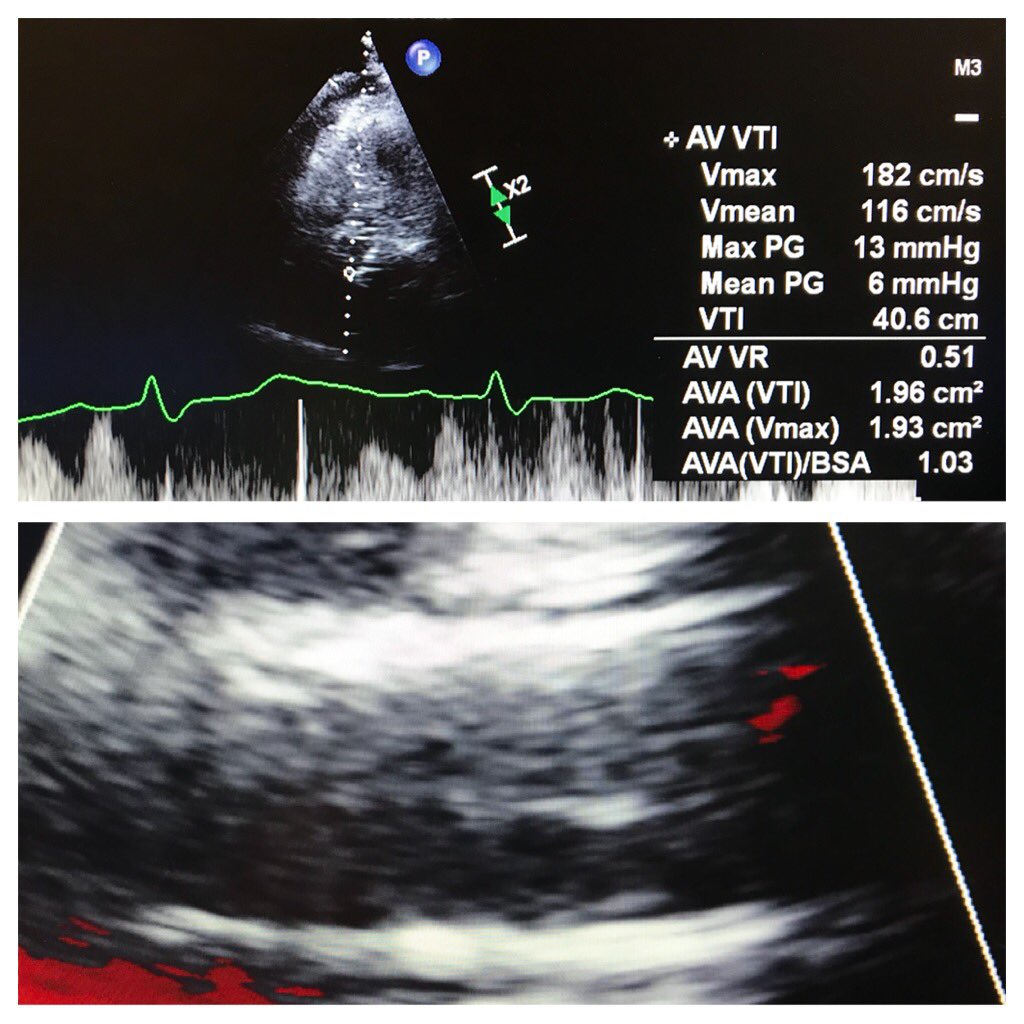

“Learning to Burn” w/ @JasonFoerst on my 1st #Transcaval access. Did #TAVR S3 23: 🚫PVL, mean AVG=2 by Cath, 6 by Echo; Final transcaval w/ minor Ao-C flow, type 1 closure. #CarilionStructural @CarilionSHD @Mjoseph3324 @SulaimanRathore @ShereeEmore @carmenhsalmon

Rahul2282Sharma's tweet image. “Learning to Burn” w/ @JasonFoerst on my 1st #Transcaval access.  Did #TAVR S3 23: 🚫PVL, mean AVG=2 by Cath, 6 by Echo; Final transcaval w/ minor Ao-C flow, type 1 closure.  #CarilionStructural @CarilionSHD @Mjoseph3324 @SulaimanRathore @ShereeEmore @carmenhsalmon